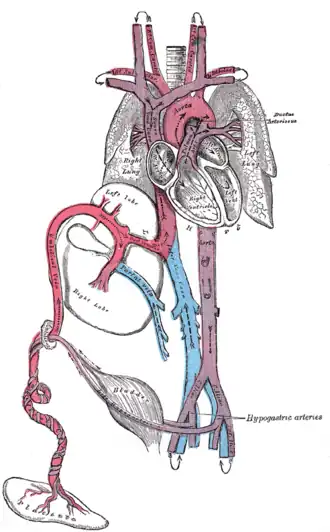

In the fetus, the ductus venosus ("DV"; Arantius' duct after Julius Caesar Aranzi[1]) shunts a portion of umbilical vein blood flow directly to the inferior vena cava.[2] Thus, it allows oxygenated blood from the placenta to bypass the liver. Compared to the 50% shunting of umbilical blood through the ductus venosus found in animal experiments, the degree of shunting in the human fetus under physiological conditions is considerably less, 30% at 20 weeks, which decreases to 18% at 32 weeks, suggesting a higher priority of the fetal liver than previously realized.[3] In conjunction with the other fetal shunts, the foramen ovale and ductus arteriosus, it plays a critical role in preferentially shunting oxygenated blood to the fetal brain. It is a part of fetal circulation.

The pathway of fetal umbilical venous flow is

umbilical vein left portal vein ductus venosus inferior vena cava eventually right atrium.